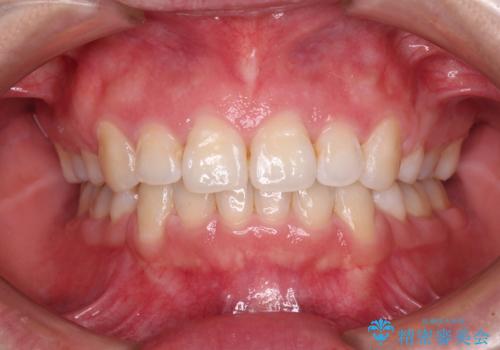

出っ歯を改善した後に真っ白な歯に 矯正歯科治療と審美歯科治療